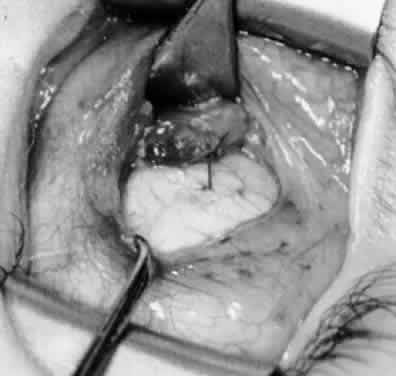

Fig. 10. The inferior oblique muscle is placed on the Green muscle hook. The exposed insertion is ready for myotomy, myectomy, disinsertion, placement of sutures for recession, or removal for the extirpation procedure.

Fig. 11. Sutures are placed into the insertion of the inferior oblique muscle before it is sectioned from the globe for the recession procedure.

Fig. 12. An Aebli scissor is placed beneath the inferior oblique muscle insertion before it is sectioned from the globe.

Fig. 13. The inferior oblique muscle is sectioned from the globe. A preplaced 6-0 Vicryl suture is attached to the insertion.